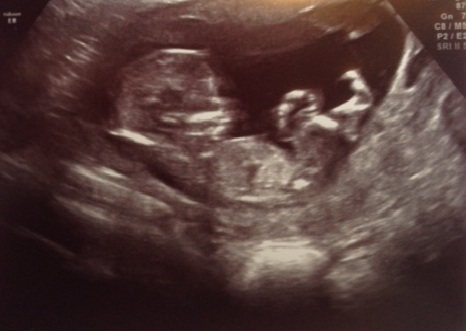

Wondering if you'd mind taking a look at my U/S pictures, taken at 13 GA.

Would be interested in whether you think girl or boy depending on skull or nub?

Attachment 18041

The first pic sort of looks like a boy nub although it doesn't point up so I'm not totally sure... Not that helpful! Sorry:/

No that's interesting you say that; on another site I've got mainly boy guesses. Which confused me, as it's out straight and seems at an angle of less than 30 degrees, but I agree it doesn't have a classic 'girly' fork at the end. It looks a bit bulbous at the end, but someone else pointed out that blobby bit is probably part of the image of the cord/leg.